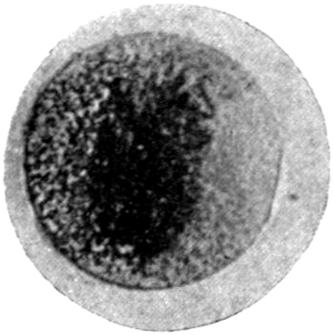

The Mechanism of Lead Absorption.

—The final method of absorption of lead particles or lead solution into the animal body remains to be considered. Experimental phagocytosis of lead particles—as, indeed, of any minute particles of substance—suspended in an isotonic solution, may be observed directly under the microscope. Lead particles show no exception to the rule, and white blood-corpuscles in a hanging-drop preparation, made by suspending them in an isotonic salt solution and serum, may be watched englobing particles of lead, and by appropriate means the ingested lead may be afterwards demonstrated. In such an experiment, much of the lead absorbed by the individual corpuscles rapidly loses its property of giving a black precipitate with sulphuretted hydrogen, and has apparently become converted into an organic compound, peptonate or albuminate.

In the section devoted to the Chemistry of Lead, it has been[21] noted that the colloidal solutions of lead are not precipitated by sulphuretted hydrogen, and that albuminates and peptonates of lead are presumably of colloidal form. There seems evidence, therefore, that the direct absorption of lead takes place by means of the phagocytes of the body, and that in them it becomes converted into a colloidal form, in which it is probably eliminated through the kidney and intestine, mainly the latter.

Further evidence of the englobement of lead particles by amœbic cells may be gained if sections of the intestines of experimental animals are examined; in the lymphoid glands particles of lead may be seen situated in the interior of the walls, and even in the cells. It does not by any means follow that these particles of lead sulphide present in the cells have been formed in situ; more probably the lead has been converted into a sulphide in the intestinal lumen itself, and subsequently taken up by the amœbic cells situated in its periphery.